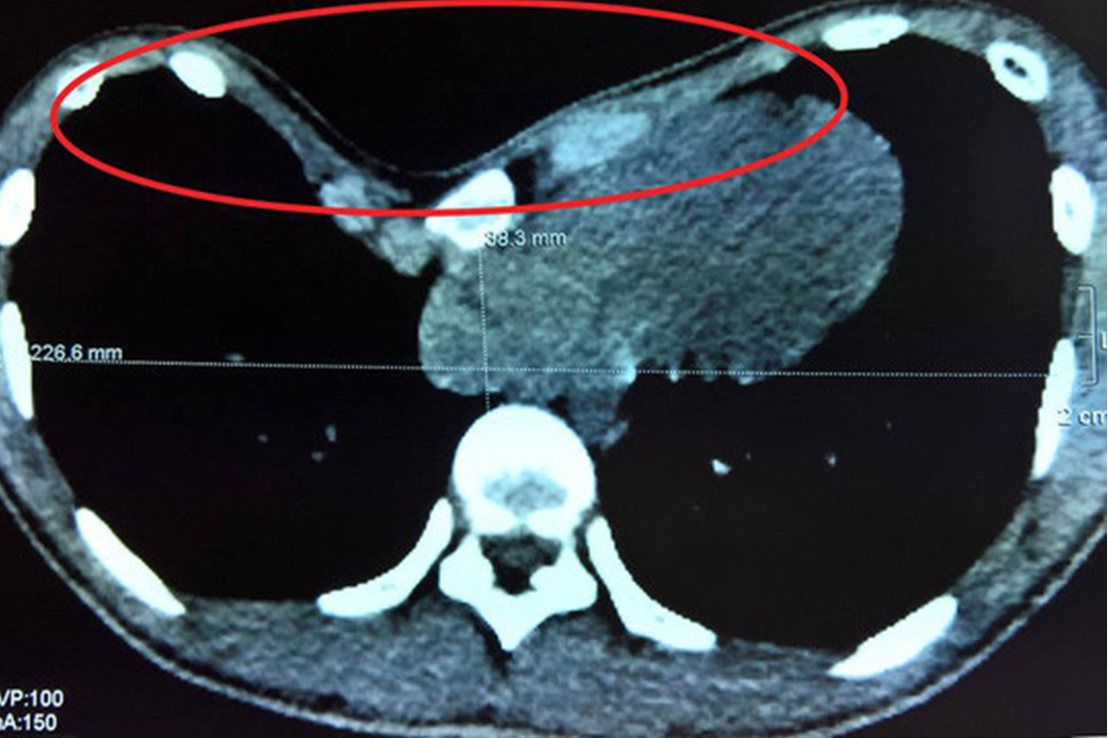

1.2 Hình ảnh chụp cắt lớp vi tính tổn thương lõm ngực bẩm sinh